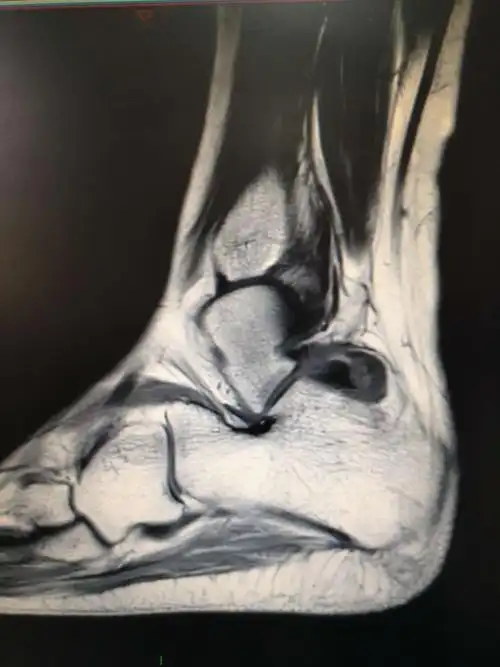

踝关节镜下切除腱鞘巨细胞瘤